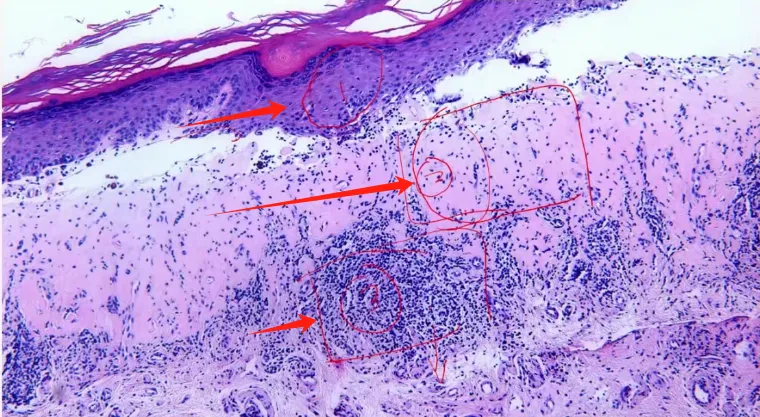

基底层明显的色素细胞(红圈),真皮内炎细胞浸润(红线),病程早期阶段病变的形态学特点非常的不特异!

这张图跟上图一样,大家要对这个病变要非常仔细的去看。